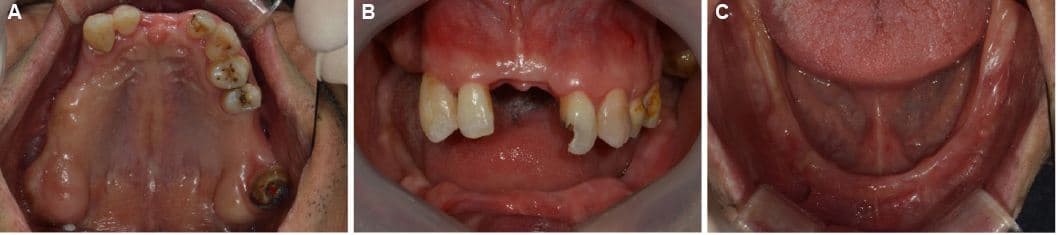

Phục hồi toàn hàm

Những trường hợp sức khỏe răng miệng bị hủy hoại hoàn toàn

được phục hồi trở lại cuộc sống bình thường

Điều trị tổng thể bởi bác sĩ chuyên khoa Phục hình

Bác sĩ phục hình của chúng tôi kết hợp tối ưu các phương pháp điều trị bao gồm Implant, răng sứ và cầu răng để tạo ra kết quả tốt nhất với chi phí hợp lý.

Trước & Sau

Implant hướng dẫn kỹ thuật số

Sau

Implant răng cửa · Bà K●● · Nữ, 50 tuổi

Implant răng cửa · Ông L●● · Nam, 60 tuổi

Implant răng hàm · Ông P●● · Nam, 50 tuổi